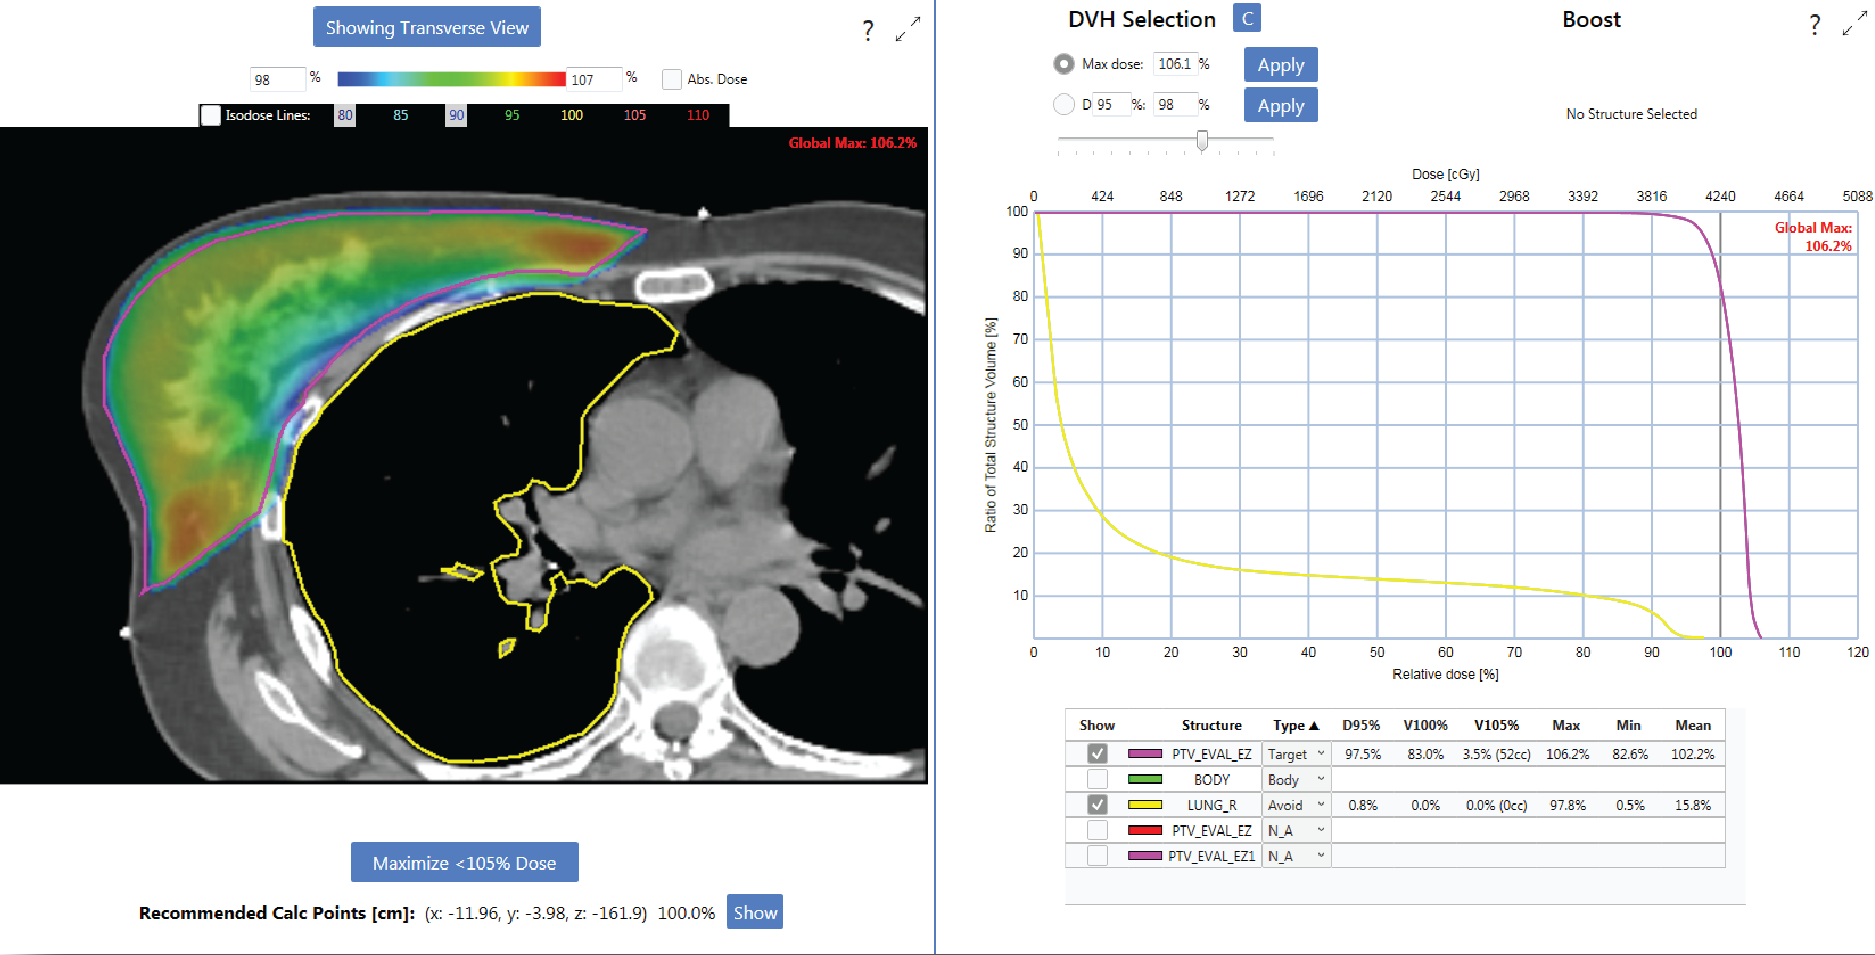

Breast Planning

EZFluence follows ASTRO’s guidelines for whole breast treatment. Automate field-in-field** and e-comp* planning. Optimize coverage while minimizing the maximum dose and V105%.

•   Preserve MLC blocking

•   Generate fluence for the flash region

•   Use on single or mixed energy plans

•   Auto-contour the PTV Eval